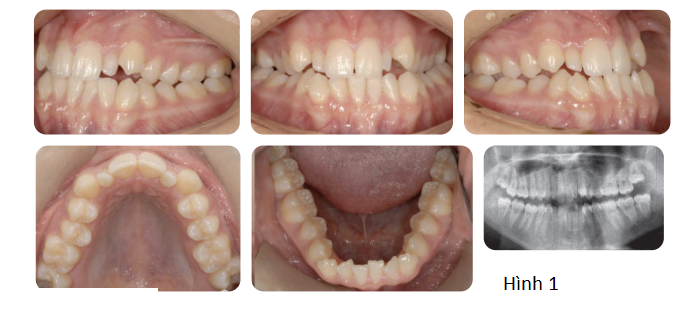

Phân tích case: Chỉnh nha tiền phẫu thuật cho bệnh nhân bị móm, hàm dưới đưa ra trước và lệch trái

Bệnh nhân có kiểu xương hạng III với thiểu sản xương hàm trên và xương hàm dưới đưa ra trước, lệch nhẹ sang bên trái. Bệnh nhân có tăng kích thước dọc, với độ lộ răng cửa tối thiểu ở tư thế nghỉ và lộ hoàn toàn khi cười. Đưa xương hàm trên ra trước sẽ giải quyết được tình trạng lõm mặt khi nhìn nghiêng và kết quả là tăng độ lộ răng cửa nhiều hơn, cho thấy có thể cần tác động vào phần trước xương hàm trên. Lực tác động vào phần sau xương hàm trên (lớn hơn lực tác động vào phần trước, nghĩa là đẩy không đồng nhất) được yêu cầu để giải quyết độ cắn trùm giảm và xu hướng cắn hở phía trước (móm). Lùi xương hàm dưới kết hợp xoay sang bên phải sẽ giải quyết được tình trạng xương hàm dưới đang nhô ra và bất cân xứng.

Qua thăm khám, bác sĩ chỉ định bệnh nhân cần chỉnh nha trước phẫu thuật hàm. Và các mục tiêu điều trị chỉnh nha bao gồm: